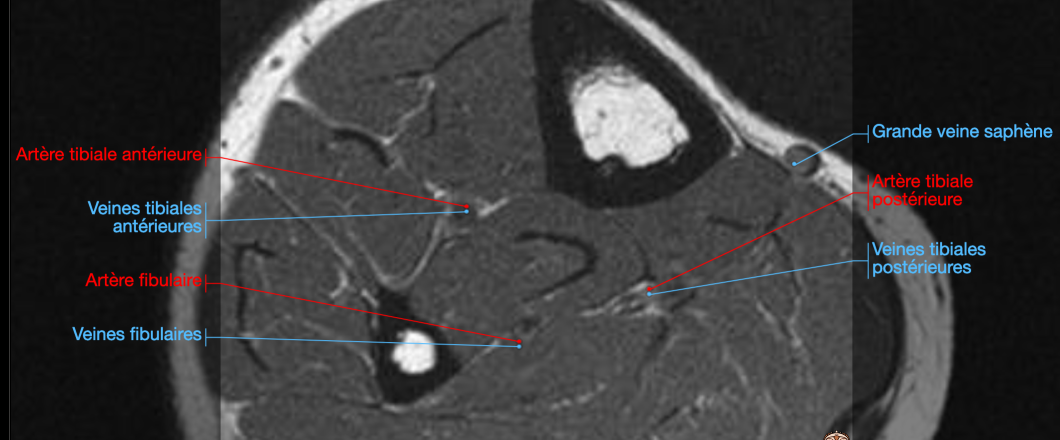

Veine tibiale antérieure

Veine péronière (fibulaire)

Veine tibiale postérieure